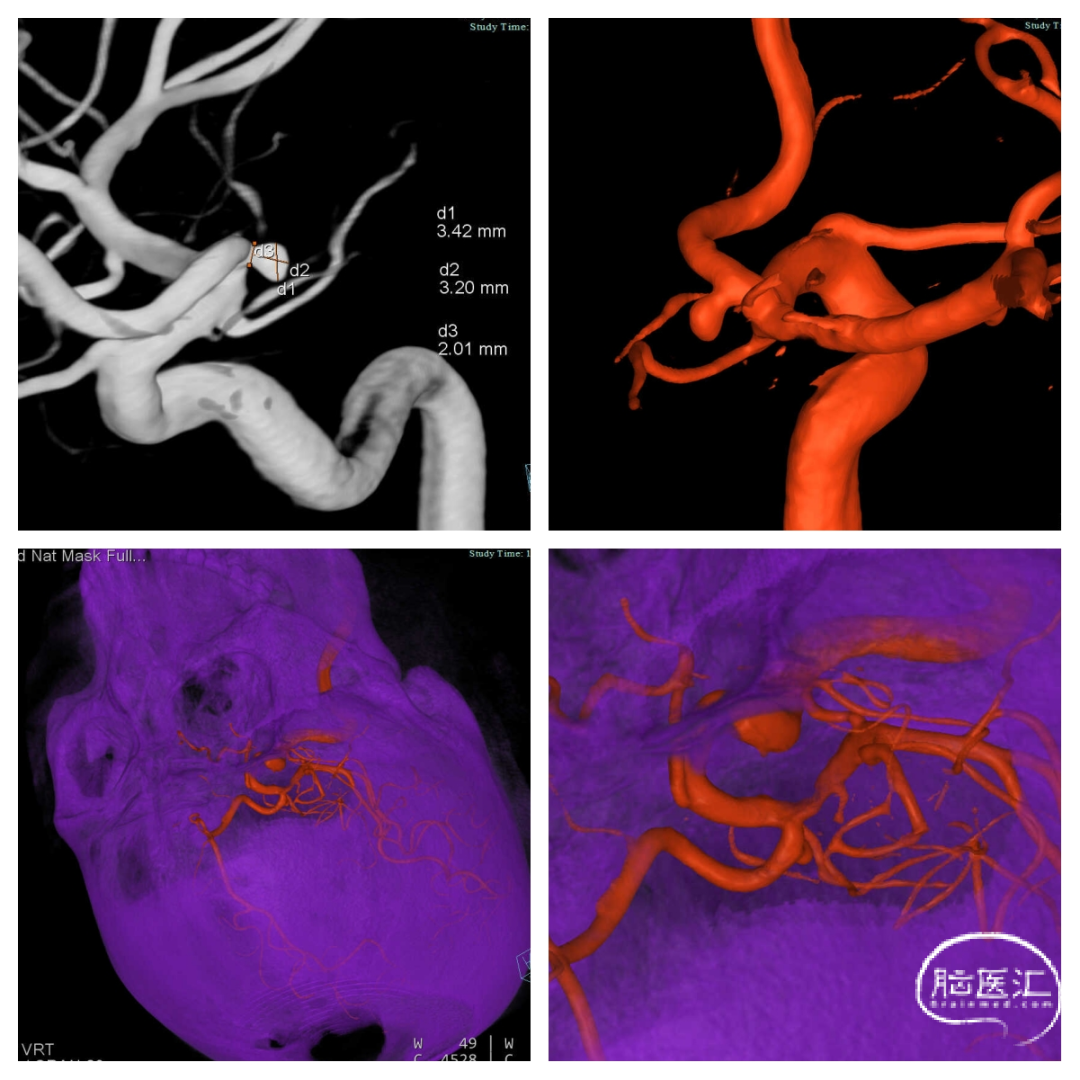

复查CT:(图4)

术后12天复查造影:动脉瘤夹闭完全,无明显残留,载瘤动脉远端有轻度狭窄(图5)。